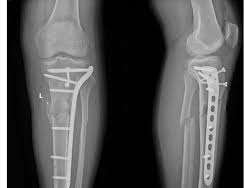

Orthopaedic Trauma Management at AIOR Trauma Center

AIOR Team is specialised in dealing with following Orthopaedic Trauma

• Complex Intra-articular (Joint Trauma)

Orthopaedic Trauma Surgeons are unique in that they specialize in complex injuries to bones, joints and soft tissues (like muscles, tendons and ligaments) throughout the entire body. Many orthopaedic specialists specialize in just one body part. Others may provide more general care but won’t treat more acute fractures, which are physically more difficult to fix. Orthopaedic trauma physicians, however, receive training in the field of orthopaedic surgery with a special focus on the treatment of fractured bones and joint realignment to promote the safe recovery and return of functionality to injured body parts. So, they often treat patients with multiple broken bones, compound fractures and fractures near a joint (like a hip or knee).Orthopaedic trauma surgeons are able to follow patients through all stages of recovery and enlist the help of other specialists, if needed, to treat complex cases. By maintaining open communication with all providers, they are able to ensure each patient receives the care needed to resume a full and active lifestyle.